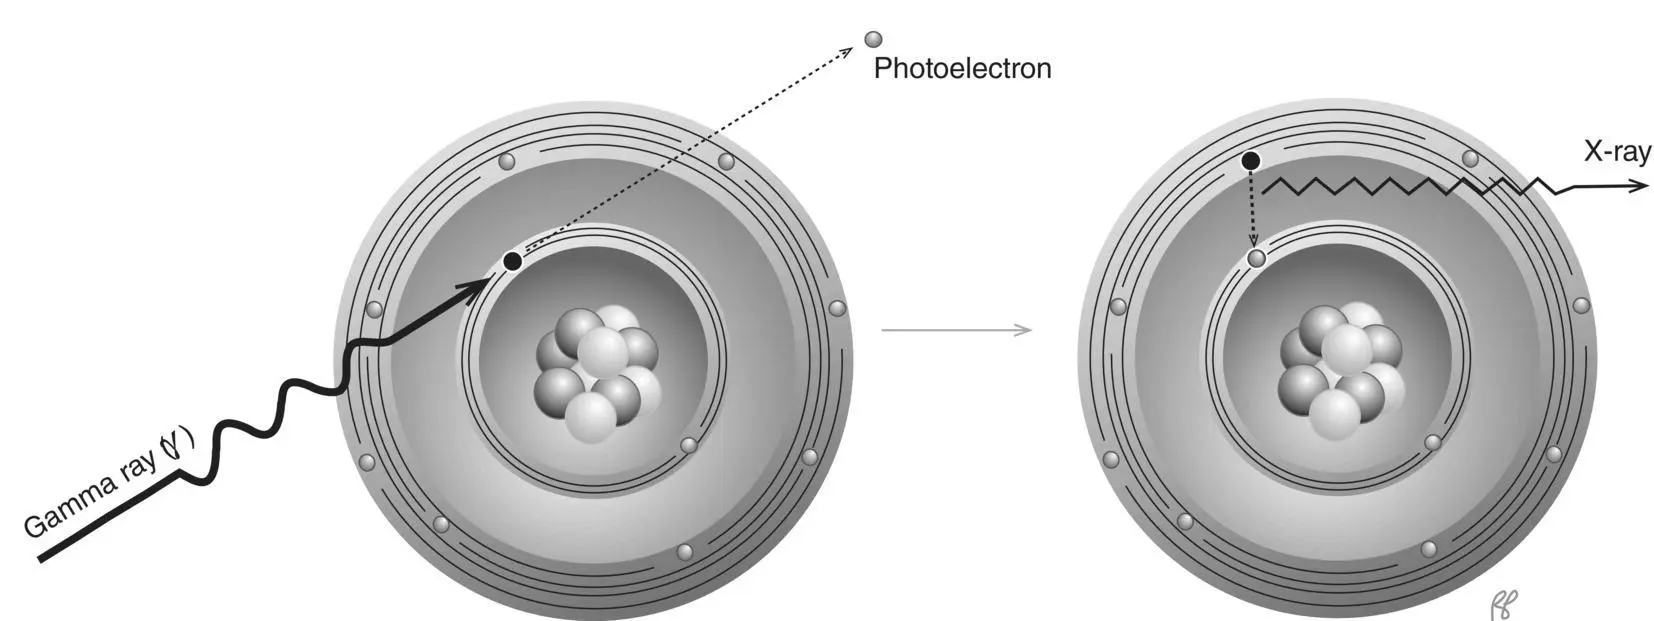

Figure 2.7 Penetrating radiation and nonpenetrating radiation.

The term penetrating radiationmay be used to describe X‐ray and gamma radiation, as they have the potential to penetrate considerable thickness of a material. Although we have just described some of the many ways photons interact with matter, the likelihood of any of these interactions occurring over a short distance is small. An individual photon may travel several centimeters or farther into tissue before it interacts. In contrast, charged particles (alpha, beta) undergo many closely spaced interactions. This sharply limits their penetration ( Figure 2.7).

Because of the strong electrical force between a charged particle and the atoms of an absorber, charged particles can be stopped by matter with relative ease. Compared to photons, they transfer a greater amount of energy in a shorter distance and come to rest more rapidly. For this reason, they are referred to as nonpenetrating radiation(see depiction of alpha and beta particles in Figure 2.7). In contrast to a photon of 100 keV which has a HVL of 4 cm in soft tissue, an electron of this energy would penetrate less than 0.00014 cm in soft tissue [1].